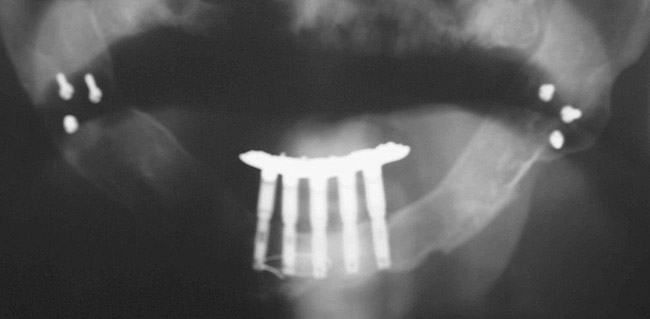

Endosseous osseointegrated dental implants have added significant and predictable treatment options that previously were unavailable for patients and clinicians.1-4 The original dental implant treatment protocol, with machined-surface, commercially pure titanium implants, was developed for use in the mandibles of edentulous patients because these patients traditionally had the most difficulty adapting to complete dentures. Screw-retained implant prostheses for mandibular edentulous patients generally consisted of cast-metal frameworks with machined cylinders incorporated into the castings. The cylinders/frameworks were screwed into abutments that had been screwed into osseointegrated dental implants (Figure 1). The precisely machined interfaces between abutments and cylinders were maintained through careful, meticulous procedures throughout the casting process (Figure 2). One of the major advantages associated with screw-retained prostheses was retrievability. However, there were numerous reports of screw loosening and/or screw fracture, along with other prosthetic complications5-7 (Figure 3).

Figure 1  Panoramic radiograph of an edentulous patient treated with five endosseous titanium implants in the anterior mandible.

Figure 1